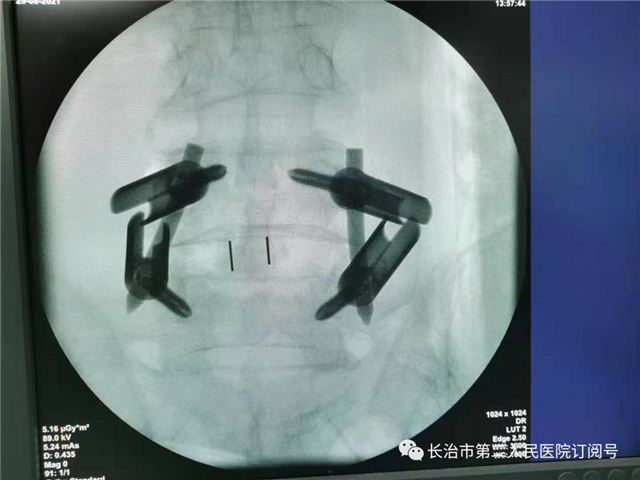

植入融合器

术后影像科室推荐